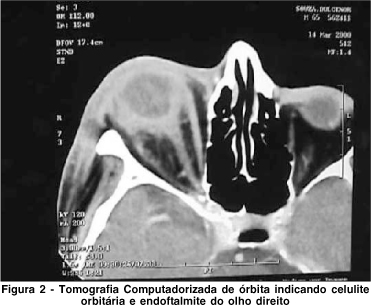

Os resultados dos exames foram normais, exceto hemograma: hemoglobina 7,8 mg/dl, hematócrito de 22,6%, 23.000 plaquetas. Fosfatase alcalina: 473 U/I, Gama GT: 404U/I. IgG para toxoplasmose: 49 U/Iml. A TC de órbita indicava celulite pré e pós septal e endoftalmite no OD (Figura 2). Na biópsia vítrea foi identificada Escherichia coli. O antibiograma indicava sensibilidade ao antibiótico usado.